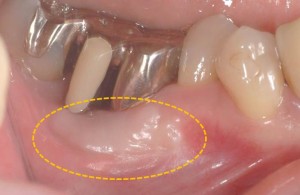

オレンジ○の部分が移植後2ヶ月になります。